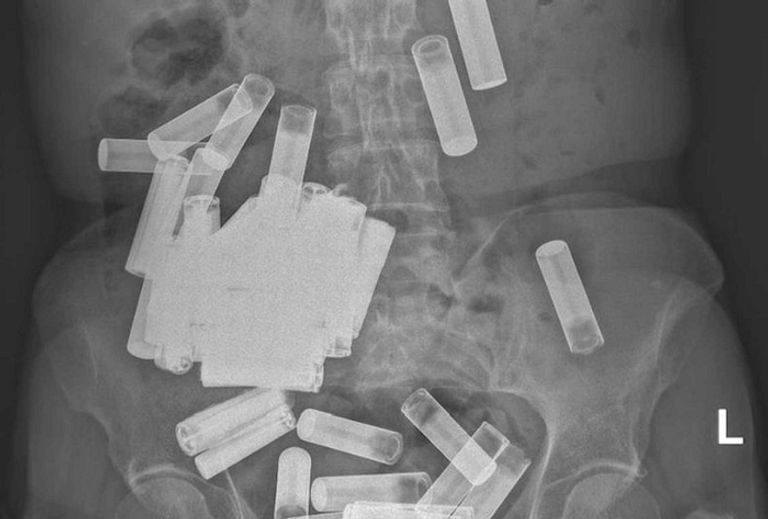

وأوضح الأطباء أنه بمجرد إجراء الأشعة السينية على جسدها تبين وجود 55 بطارية AA وAAA في البطن والقولون، ولفتوا إلى أن المرأة أصيبت بتقلصات في المعدة وانتفاخ بسبب وزن البطاريات التي ابتلعتها.

وأجرى الأطباء للسيدة عملية جراحية لانتشال 46 بطارية، بعدما طرد جسمها 5 بطاريات، وسحبوا 4 أخرى من القولون.